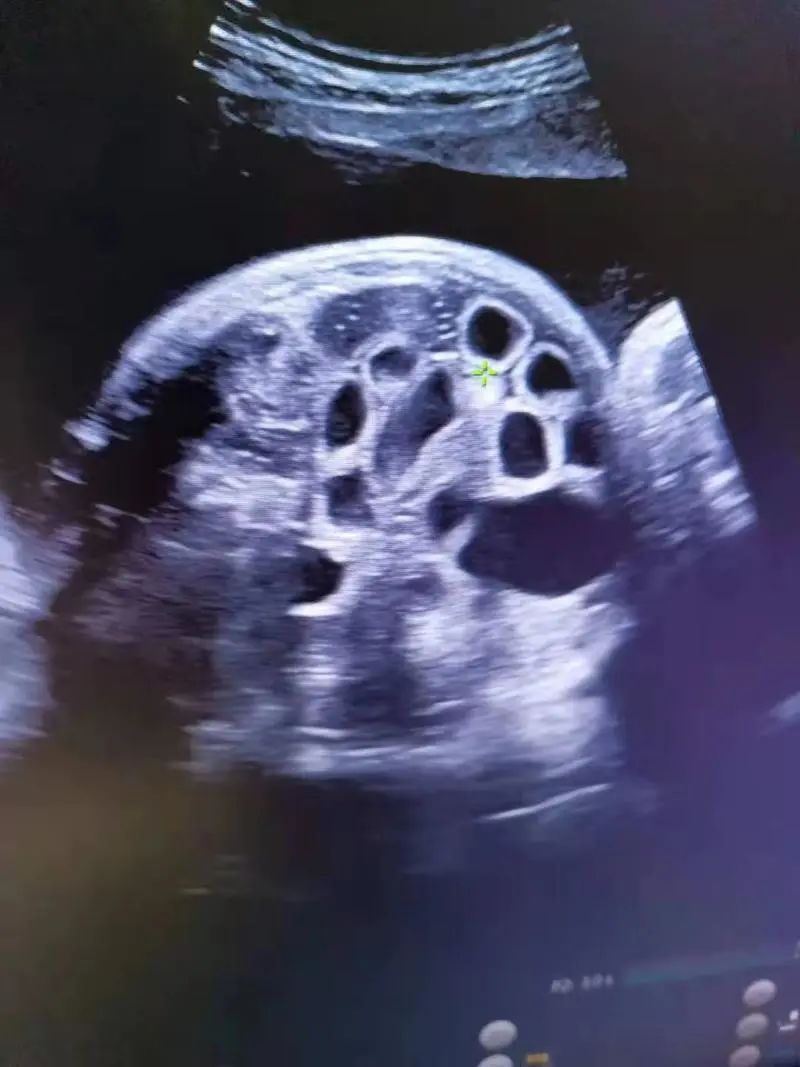

b超发现羊水过多,胃泡增大,肠管扩张

胎儿胃泡大小5.0*1.6cm是正常吗!请问标准 急急